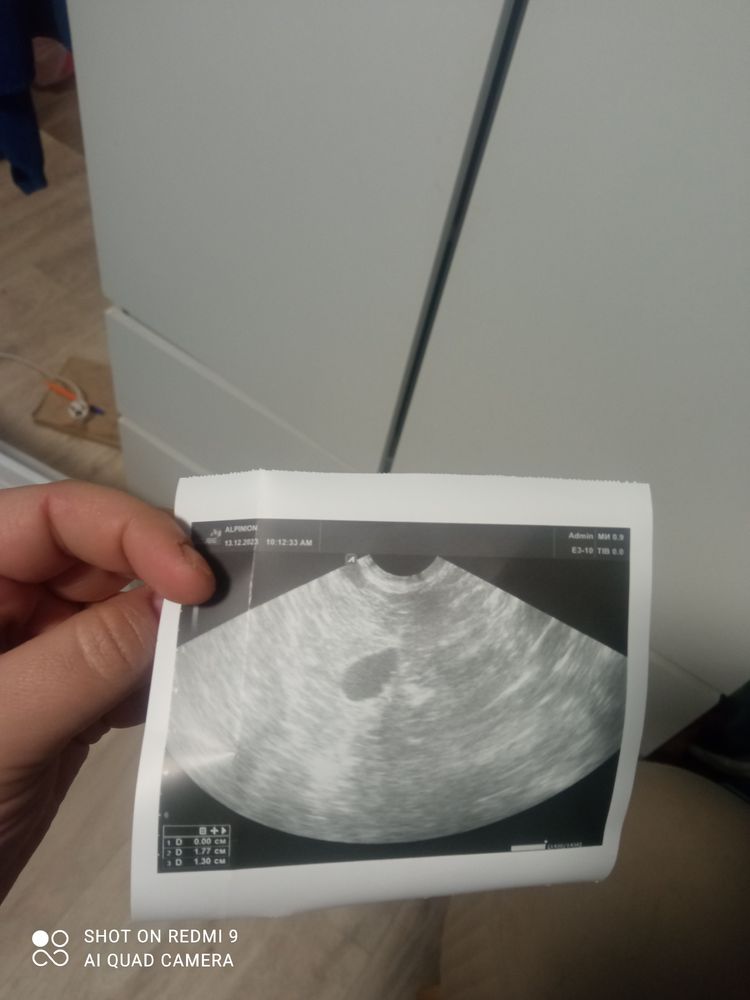

Анастасия , может поветрие на задержку перед нг? 😁 Похож на плодное яйцо, смотрела в интернете такие же фото есть...

3 день задержки с посмотрите пожалуйста Не дождалась я вечера